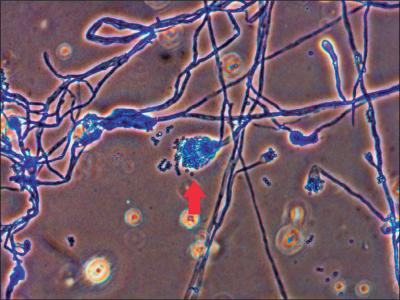

दिल्लीत नव्या फंगसमुळे होणाऱ्या मृत्यूंमुळे चिंतेत भर पडली आहे. एम्समध्ये दोन रुग्णांना एस्परजिलियस लेंटुलस नावाच्या फंगसची लागण झाली. या प्रकारच्या फंगसवर कोणत्याही औषधाचा परिणाम होत नाही.

क्रॉनिक ऑब्स्ट्रक्टिव पल्मोनरी डिजीजचा सामना करत असलेल्या दोन्ही रुग्णांचा उपचारादरम्यान मृत्यू झाला. एस्परजिलियस लेंटुलस फुफ्फुसावर परिणाम करतं. २००५ मध्ये वैद्यकीय जगताला या फंगसची औषध पटली. तेव्हापासून आतापर्यंत अनेक देशांमध्ये एस्परजिलियस लेंटुलसचे रुग्ण आढळून आले आहेत.

पहिल्या रुग्णावर एका खासगी रुग्णालयात उपचार सुरू होते. मात्र प्रकृतीत सुधारणा न झाल्यानं त्यांना एम्समध्ये हलवण्यात आलं. त्यांना Amphotericin B आणि ओरल Voriconazole इंजेक्शन्स देण्यात आली. मात्र महिन्याभरानंतरही त्यांची प्रकृती सुधारली नाही आणि त्यांचा मृत्यू झाला.

दुसऱ्या रुग्णाला ताप, खोकला आणि श्वास घेण्यास त्रास सुरू होता. त्यासाठी त्याला एम्समध्ये दाखल करण्यात आलं. त्यालाही Amphotericin B देण्यात आलं. मात्र आठवड्याभरातच शरीरातील अनेक अवयव निकामी झाल्यानं त्याचा मृत्यू झाला.